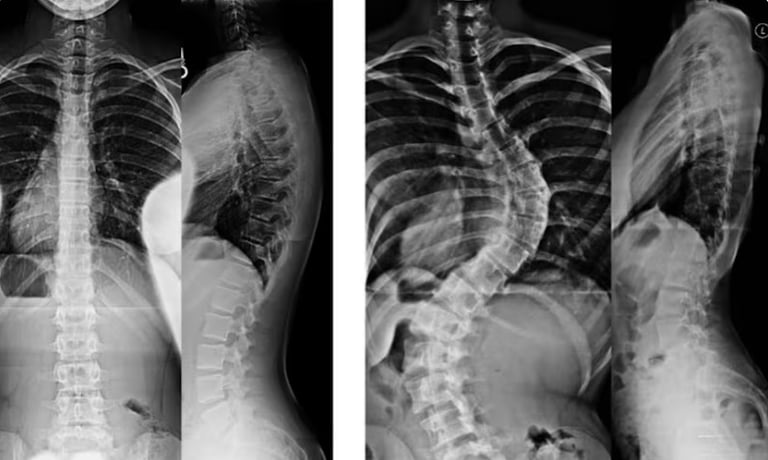

الجنف هو حالة بنيوية تصيب العمود الفقري، حيث ينحني العمود الفقري بشكل غير طبيعي من جانب إلى آخر، وغالبًا ما يصاحبه دوران حول محوره بدلًا من بقائه مستقيمًا عند النظر إليه من الخلف. وقد يأخذ هذا الانحناء شكل حرف S أو C، ويظهر الجنف بشكل أكثر شيوعًا خلال فترات النمو السريع مثل مرحلة المراهقة، إلا أنه قد يحدث في أي عمر.

في العمود الفقري السليم، تُشكِّل الفقرات عمودًا رأسيًا مع انحناءات طبيعية خفيفة من الأمام إلى الخلف. أمّا في حالة الجنف، فإن العمود الفقري ينحني أيضًا بشكل جانبي في المستوى الأمامي، وقد يصاحبه دوران، مما قد يؤدي إلى عدم التناسق في وضعية الجسم والمظهر العام.

ويُؤخَذ تشخيص الجنف عادةً بعين الاعتبار عندما يتجاوز انحناء العمود الفقري حدًا معيّنًا في الفحوصات التصويرية، وغالبًا ما يتم قياس ذلك باستخدام زاوية كوب (Cobb angle) في صور الأشعة السينية.

يبدأ تشخيص الجنف بتقييم سريري يشمل أخذ تاريخ صحي مفصّل وفحصًا بدنيًا شاملًا. وقد يلاحظ الممارس الصحي وجود عدم تماثل في مستوى الكتفين أو الوركين أو الخصر، أو اختلافًا في وضعية الجسم. وتُستخدم الفحوصات التصويرية، مثل الأشعة السينية، لتأكيد وجود الانحناء وقياس درجة شدّته.